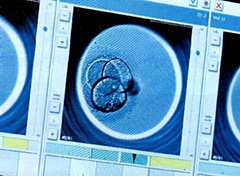

通常の顕微鏡での胚の様子

紡錘体が可視化する